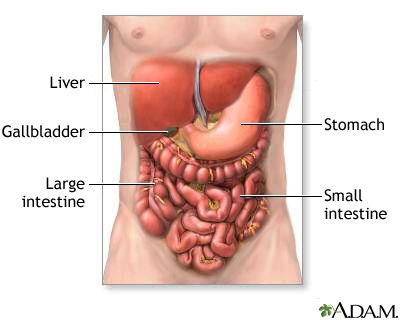

Liver metastases refer to cancer that has spread to the liver from somewhere else in the body.

Liver metastases are not the same as cancer that starts in the liver, which is called hepatocellular carcinoma.

- Pain, often in the upper right part of the abdomen